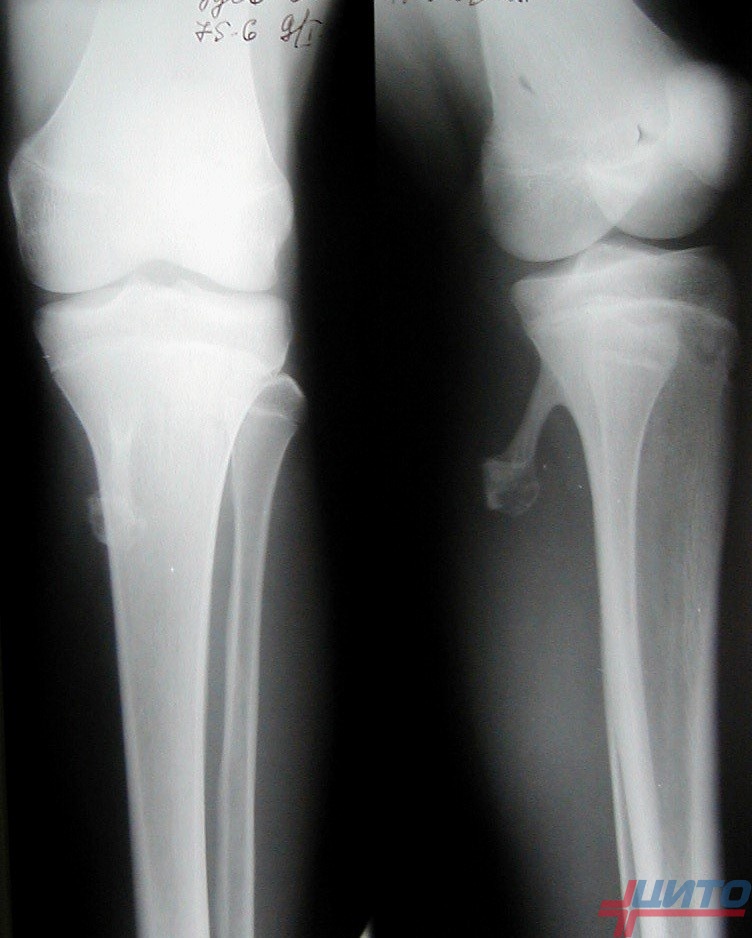

| Рентгенография | Может показать зону уплотнения кости (склероз) и иногда само «гнездо» в виде небольшого просветления. Однако на ранних стадиях или при сложной локализации рентгенограммы могут быть неинформативны. | Это первичный, базовый метод, позволяющий заподозрить проблему и исключить другие патологии (например, переломы). |

| Компьютерная томография (КТ) | Является «золотым стандартом» диагностики остеоид-остеомы. КТ с высокой точностью визуализирует маленькое гнездо опухоли и зону склероза вокруг него. | Позволяет безошибочно подтвердить диагноз, определить точные размеры и расположение гнезда, что критически важно для планирования лечения. |